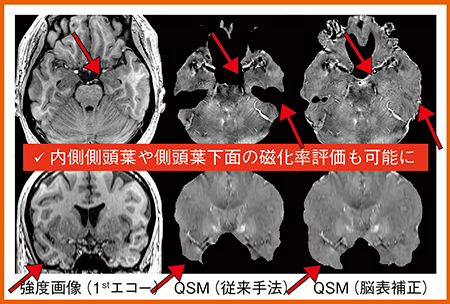

従来のQSM解析手法では,磁化率差が大きい脳表部分の解析ができなかったが,日立は脳表背景磁場を多項式近似した推定法を開発し,全脳の局所磁場を高精度に推定することで,脳表までの全脳QSM解析が可能となった。これにより,ADにおける内側側頭葉や側頭葉下面の鉄沈着を評価することができる(図3)。

図3 脳表補正のQSM解析(W.I.P.)

●中間解析結果

多施設共同臨床研究の中間解析結果を紹介する。AD群(25名)と健常群(86名)を対象とし,AALテンプレートの120領域のうちAD群で磁化率が上昇する領域について,従来手法QSMと脳表補正QSMで評価した。その結果,AD群と健常群で有意差があったのは,従来手法QSMでは7領域,脳表補正QSMでは15領域であった9)。脳表補正QSMでは脳表まで磁化率評価が可能なため,有意差のある領域が増加したと考えられる。